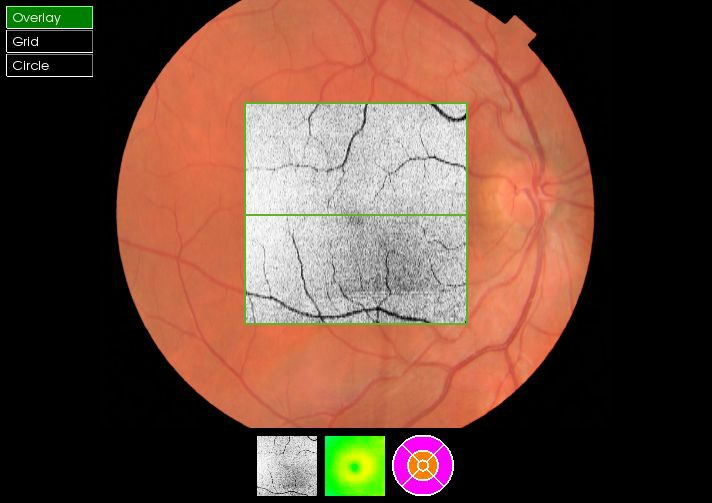

As well as the 3D scan, our instrument also takes a photograph of the eye in high resolution. This allows us to pin point any area of concern to review in depth.

A 3D section of the layers ofthe retina and vitreous jellyA 3D section of the layers of the retina and vitreous jellyAge-related Macular Degeneration Dry FormAge-related Macular Degeneration Dry FormAge-related Macular Degeneration Wet FormAge-related Macular Degeneration Wet FormThe vitreous (jelly) pulling on the retinaThe vitreous (jelly) pulling on the retinaImage of Retina (back of the eye)Image of Retina (back of the eye)